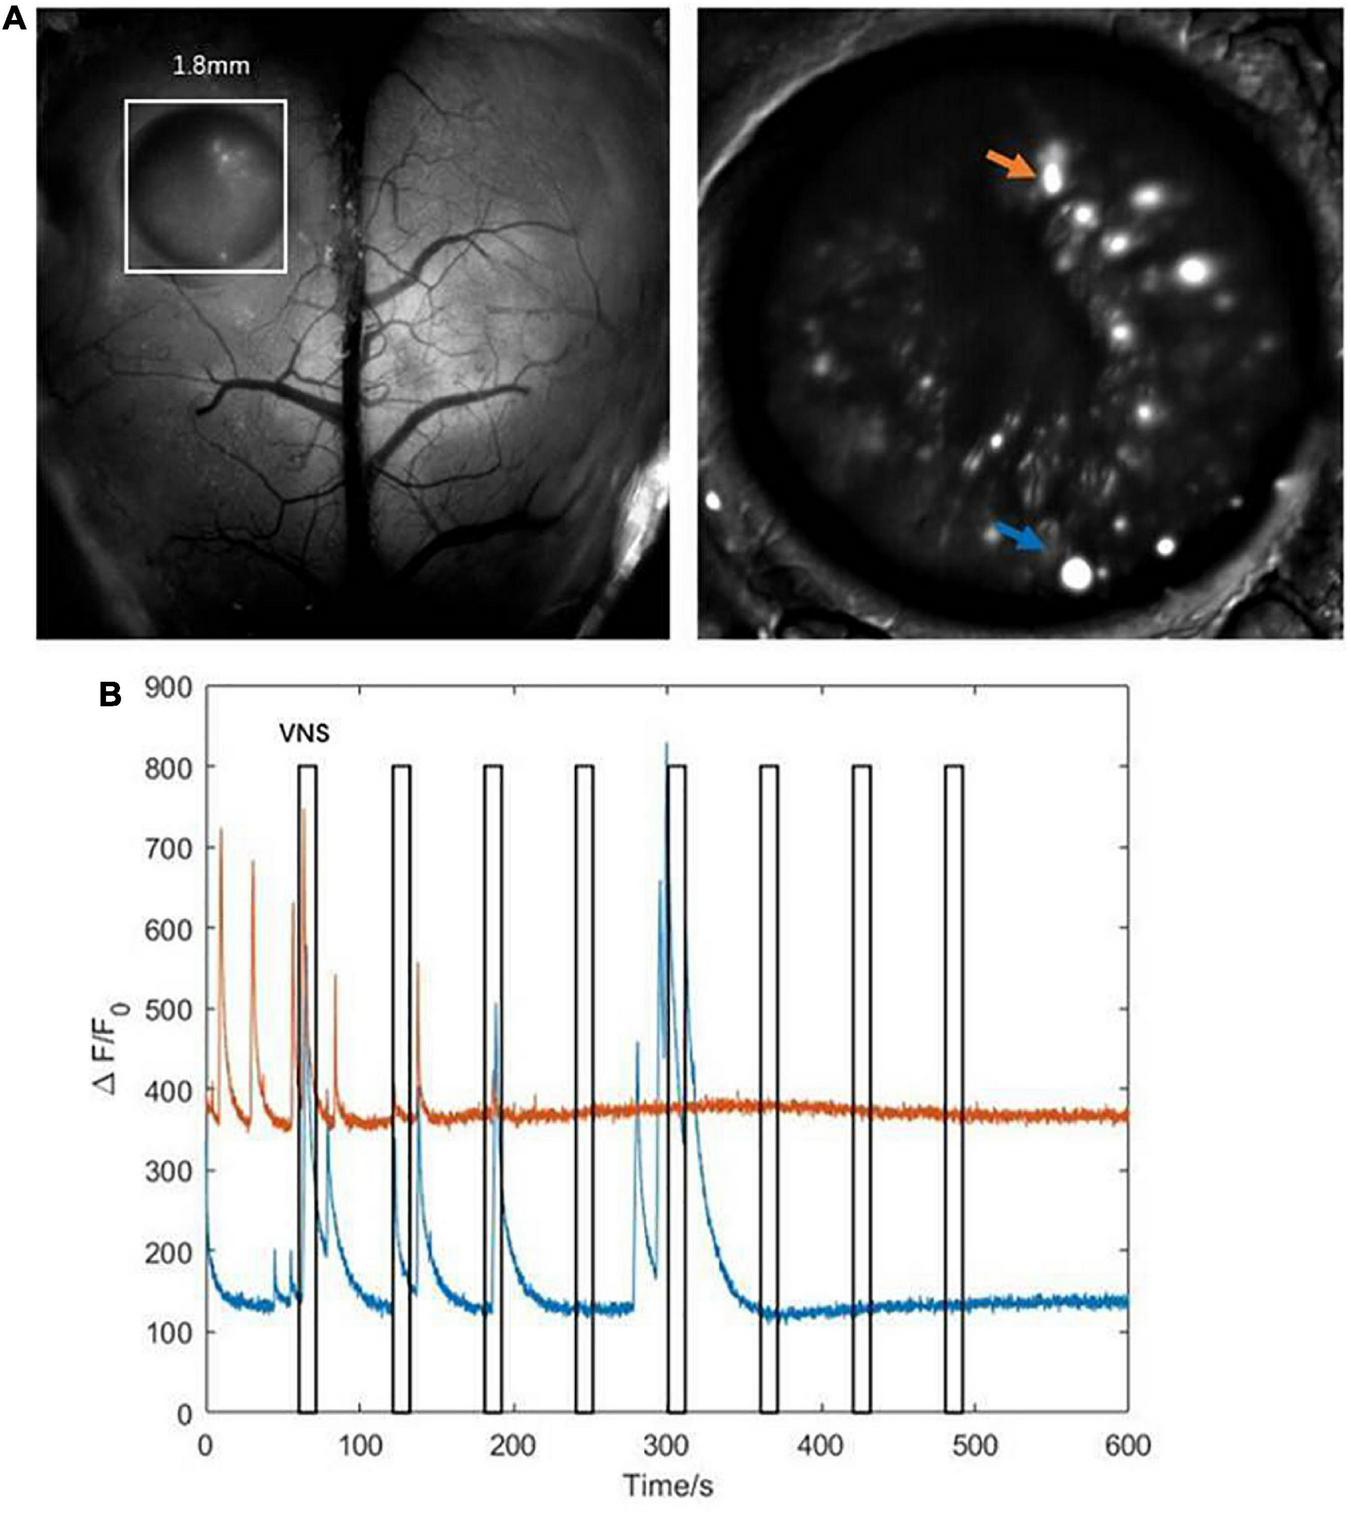

The results above showed that the activities of several neurons in the hippocampal CA1 were tightly correlated with VNS (Figure 5A). We further extracted two typical neurons to achieve the curve of neuronal calcium signaling. We analyzed that one neuron (orange curve) showed inhibition characteristics, and the other neuron (blue curve) showed activation characteristics in response to VNS application (Figure 5B). Therefore, we speculated that different types of neurons had varied responses to VNS application.

FIGURE 5

Characteristics of calcium signaling of neurons in the hippocampal CA1. (A left) The hippocampal CA1 region (white square: 1.8mm × 1.8mm); (right) two typical neurons extracted from hippocampal CA1 (orange arrow and blue arrow). (B) The curve diagram of neuronal activities of the two neurons (blue curve and orange curve corresponding to blue arrow and orange arrow shown in (A), respectively). Narrow gray rectangles indicate time of each VNS application (lasting 10 s). Y-axis indicates neuron numbers.